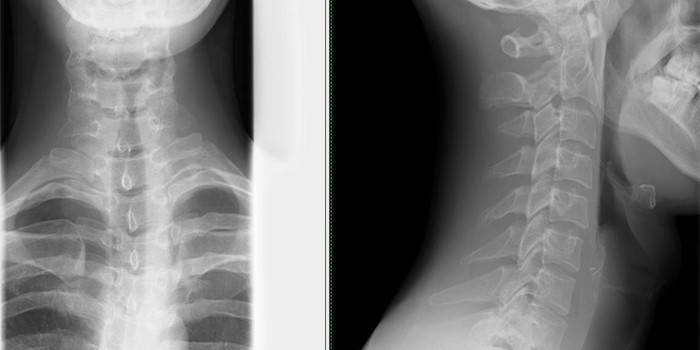

Que tipo de exame deve ser feito para dores de cabeça

O exame deve começar com um apelo a um terapeuta que, depois de ouvir suas queixas, encaminhará você a um neurologista, otorrinolaringologista, ortopedista, osteopata ou optometrista. Após um exame geral, é prescrito um diagnóstico, cujos métodos dependem da sintomatologia específica. O paciente é prescrito:

- Encefalograma: realizado com suspeita de osteocondrose, hipertensão;